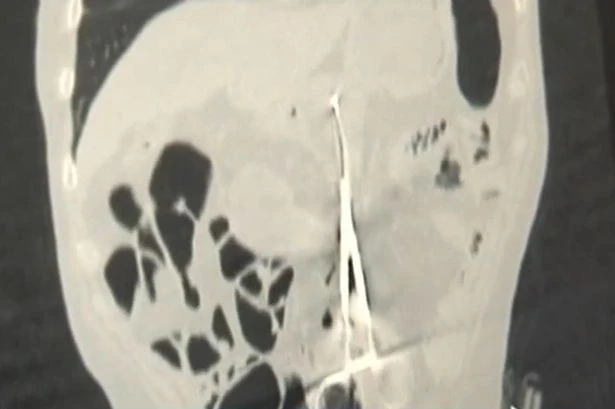

Karp Ponomaryov (53 tuổi, Kazakhstan) đã trải qua một cuộc phẫu thuật để cứu mạng sống 12 năm trước. Nhưng các bác sĩ vụng về đã bỏ quên 1 cái kéo phẫu thuật dài 20 cm trong bụng ông.

Tuy nhiên, một tháng trước, ông bắt đầu cảm thấy ăn không ngon miệng và sụt cân. Karp đã phải đi khám bệnh. Bác sĩ chụp X-quang Baurzhan Aybaev cho biết: “Tôi chưa bao giờ thấy bất cứ thứ gì như thế này. Thỉnh thoảng cũng có bác sĩ để quên bông gạc trong người bệnh nhân, nhưng một dụng y tế lớn như vậy thì nên tránh sai lầm hoặc ít nhất cũng nên phát hiện sớm hơn”.